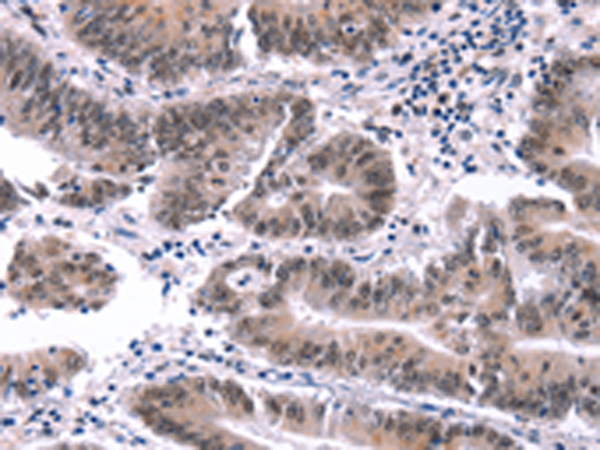

分类: 科研抗体货号: P04181别名: JBP1, SKB1, IBP72, SKB1Hs, HRMT1L5应用: WB,IHC反应种属: Human, Mouse, Rat